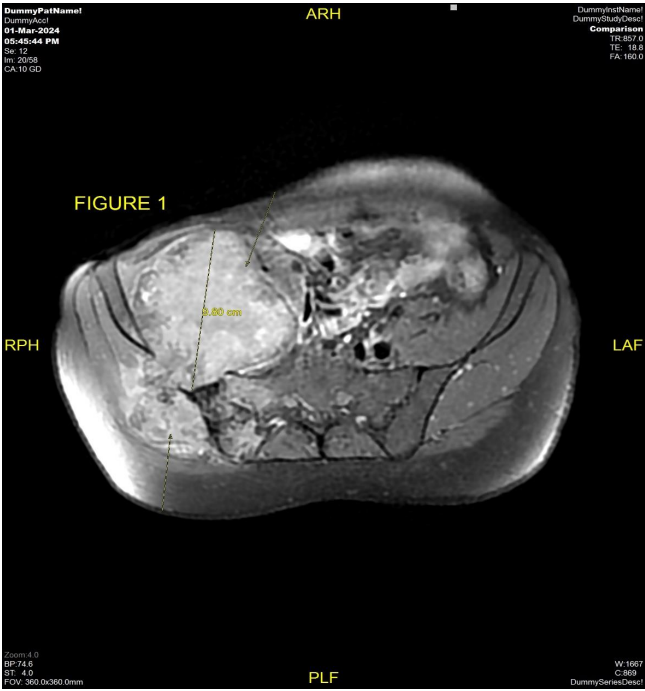

The patient underwent MRI pelvis (Fig 1 & 2) and PETCT (Fig 3 & 4) for initial evaluation (03/2024) at our institute which showed ill-defined large altered signal intensity heterogeneously enhancing mass in the right lumbar region with both intra as well as intrapelvic component by causing erosion of the right iliac bone involving the adjacent iliopsoas and gluteus muscles with central necrosis. On PET-CT scan the lesion showed significant FDG uptake with no other abnormality in the rest of the scan. Text the patient was planned for neoadjuvant chemotherapy and then for surgery. Patient took 2 cycles of neoadjuvant chemotherapy (Holoxan and Adriamycin), but after 2 cycles of chemotherapy response evaluation MRI was done (01/07/2024) (Fig 5) which showed increase in the size of lesion, so patient was planned for targeted therapy ie tyrosine kinase inhibitors, Pazopanib.

Figure 1 & 2: MRI pelvis dated 03/2024 axial and coronal view T1 post-contrast sequence shows ill-defined heterogeneously enhancing necrotic mass measuring approximately 9.8 cm in AP dimension is seen involving the right lumbar and pelvic region causing erosion of the adjacent right iliac bone and transverse process of S1 and S2 Vertebrae with both intra as well as extrapelvic component.

Figure 1

Figure 2